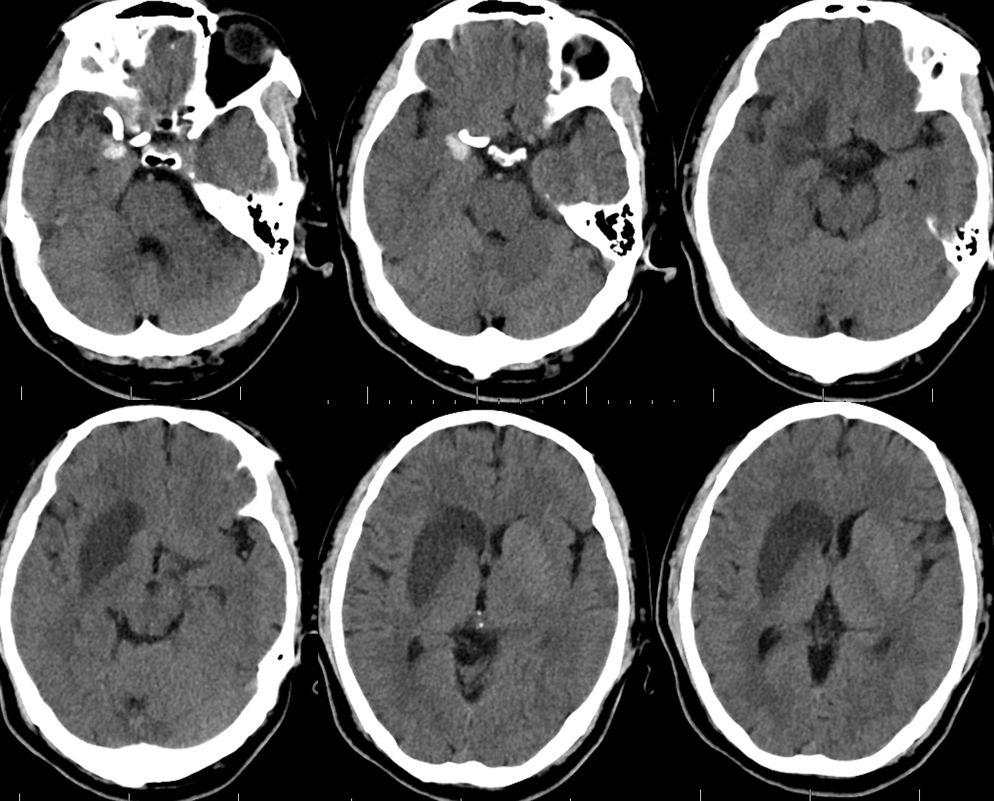

1、术后18小时CT(图五)。

治疗颅内动脉瘤新型密网支架,pipeline治疗椎动脉夹层动脉瘤

图五

术后3天CT(图八)。

图八